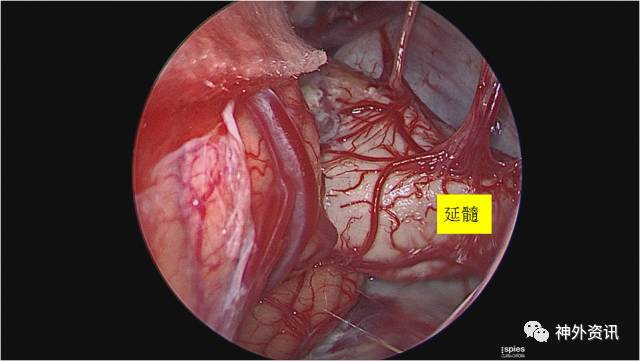

肿瘤巨大位于脑干周围广泛区域,涉及血管神经繁杂,采用神经内镜和显微镜结合,完整保留所有颅神经和血管分支,术后患者无任何并发症,黄国栋教授对此次手术有以下总结:

1. 本例胆脂瘤手术难点主要是在于肿瘤范围很广,脑干腹侧、幕下小脑上、脚间池、桥前池及血管神经间隙均有肿瘤粘连、包裹,手术要求能尽量全切除肿瘤,锐性分离保护所有颅神经及重要血管,减少小脑和脑干的牵拉。

2. 显微镜切除部分肿瘤后,采用神经内镜下切除残余肿瘤,便于在零牵拉的状态下切除脑干腹侧及对侧、脚间池、桥前池及各个血管、神经间隙的肿瘤,内镜操作过程中千万注意视野后方的内镜和器械移动可能对神经牵拉和切割。